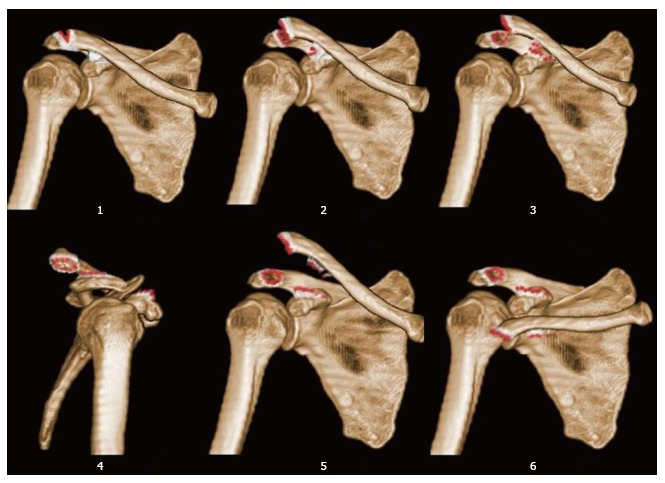

Contributor: Aaron Lessen, MD Educational Pearls: There are many techniques for reducing a shoulder dislocation A recent study discussed a new variation of closed reduction technique: wrist-clamping shoulder-lifting The patient is in a sitting position The provider holds the wrist of the injured arm with both hands and slowly rotates the arm to 90 degrees of abduction and 60 degrees of external rotation After this traction, the arm is slowly moved to 45 degrees of abduction and 60 degrees of external rotation The provider then secures the patient's wrist between the provider's knees and places their hand on the axilla to gently lift the shoulder upward for successful reduction There were 36 patients with shoulder dislocations in this study, and all 36 dislocations were successfully reduced with this technique There were no neurovascular complications or fractures No sedation or medication was required All procedures were performed by a single provider without assistance References Dai W, Liu L, Zong S, Zhou Y, Zheng J, Li X. An original closed reduction technique for acute shoulder dislocation: the wrist-clamping and shoulder-lifting. Int J Emerg Med. 2025 Mar 26;18(1):60. doi: 10.1186/s12245-025-00866-8. PMID: 40140973; PMCID: PMC11948627. Summarized by Meg Joyce, MS2 | Edited by Meg Joyce & Jorge Chalit, OMS4 Donate: https://emergencymedicalminute.org/donate/